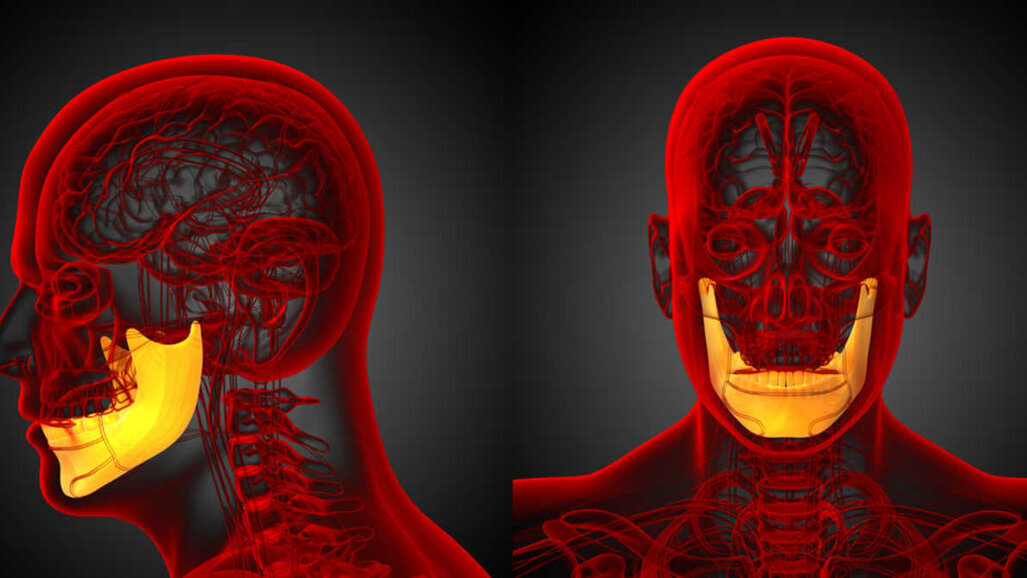

Vědci vytvořili obdélníkový defekt v dolních čelistech ovcí. Vyrobili šablonu pro 3D tisk a vytiskli implantovatelnou formu a distanční vložku, obojí z PMMA, známého také jako kostní cement. Úkolem distanční vložky bylo podporovat hojení a zabránit zjizvené tkáni, aby zaplnila oblast defektu.

Ze zvířecího modelu žebra odstranili dostatek kosti, aby odkryli periost, který sloužil jako zdroj kmenových buněk a cév pro implantaci štěpového materiálu do formy. Testované skupiny dostaly rozdrcenou kost žebra a syntetické materiály na bázi fosforečnanu vápenatého tvořící biologicky kompatibilní základ štěpu.

Forma s otevřenou částí žebra pro vytvoření těsného rozhraní zůstala na místě po dobu devíti týdnů, pak byla odebrána a přenesena do místa defektu, kde nahradila distanční vložku. Na zvířecích modelech se nová kost propojila se starou a kolem narostly měkké tkáně a oblast pokryly.